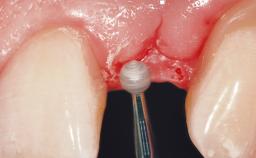

A 30-year-old female patient had lost tooth 21 and was referred to our clinic for consultation and treatment. Due to advanced apical infection, tooth 21 had been extracted two months earlier at another clinic and an acrylic-resin tooth had been bonded to the adjacent teeth. The patient desired implant treatment to avoid any damage to the adjacent natural teeth. While the patient had no history of any systemic disorder, she was a heavy smoker and exhibited medium to advanced periodontitis in the entire jaw. After the initial treatment to achieve a pocket probing depth of less than 4 mm and no bleeding on probing, a decrease in the height of the papillae mesial and distal to the extraction site and overall gingival recession were observed.

Bone Augmentation Horizontal|Staged

Augmentation Materials Autogenous chips|Membrane